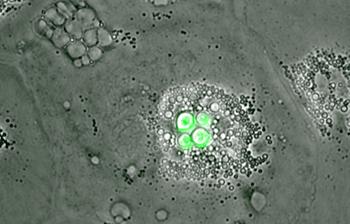

Now, a team from the University of Sheffield have shown that a particular white blood cell within the bird's blood system, called a macrophage, is able to completely block the growth of Cryptococci.

"By studying bird cells under the microscope, we have seen that macrophage cells have the ability to completely block the growth of the fungus, which can be fatal in humans.